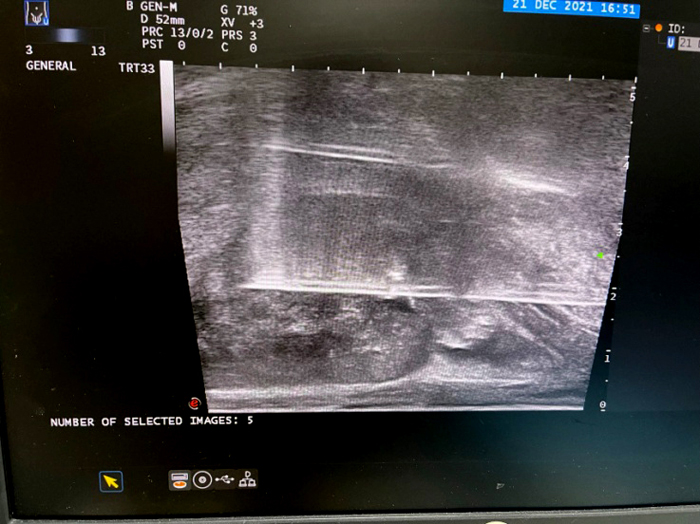

淋巴清掃術后,淋巴管囊腫置管引流并硬化

3、超聲介入置管引流和藥物注射治療

具有定位準確、操作安全的優勢,適用于肺膿腫、肝膿腫、腎膿腫、脾膿腫、盆腔膿腫、結核膿腫的引流;胸腔、腹腔積液的引流;尿路梗阻腎積水的經皮置管引流;梗阻性黃疸經皮膽道置管引流;急性膽囊炎的經皮膽囊置管引流解壓治療等。